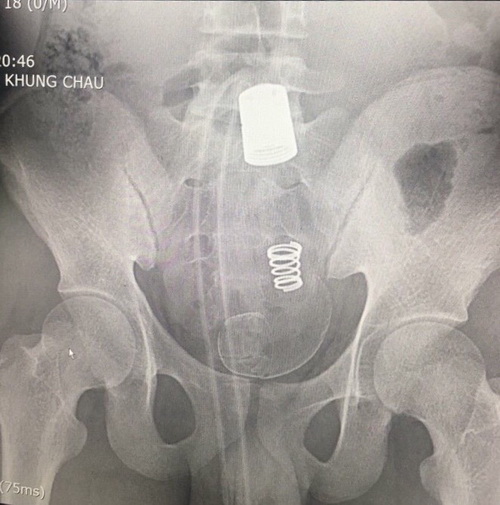

Tại BVĐK tỉnh Hải Dương, ngay sau khi thăm khám, bệnh nhân đã được chuyển đến khoa Ngoại tiêu hoá – tổng hợp. BS.Bùi Xuân Hiền, Trưởng khoa Ngoại Tiêu hoá - Tổng hợp – BVĐK tỉnh Hải Dương cho biết, qua thăm khám và làm các xét nghiệm cận lâm sàng các bác sĩ phát hiện có hình ảnh dị vật cản quang rất lớn trong ổ bụng. Tiến hành thăm khám hậu môn các bác sỹ phát hiện có dị vật hình ống silicon, rất chắc, không lấy được qua đường hậu môn, có chảy máu niêm mạc đường ruột.

Hình ảnh dị vật cản quang lớn trong ổ bụng (ảnh BSCC)

Đây là trường hợp dị vật đại trực tràng lớn và là lần đầu tiên các bác sĩ khoa Ngoại tiêu hoá – tổng hợp, BVĐK tỉnh Hải Dương bắt gặp và xử trí. Với dị vật khổng lồ như thế này, bệnh nhân không thể tự đại tiện ra được. Nếu không xử trí sớm, sẽ để lại hậu quả rất nghiêm trọng như tắc ruột, vỡ ruột thậm chí nguy hiểm đến tính mạng.

Ngay sau khi được chẩn đoán bệnh kíp trực đã hội chẩn và bệnh nhân được chỉ định phẫu thuật cấp cứu. Tuy nhiên không rõ lý do gia đình lại không đồng ý phẫu thuật ngay. Phải trải qua nhiều lần kiên trì động viên và giải thích tình trạng bệnh gia đình mới đồng ý phẫu thuật vào sáng hôm sau vào viện. Kíp phẫu thuật đã mở bụng, mở đại tràng sigma lấy được cả đoạn vòi nước và đầu xả dài khoảng 45 cm. Dị vật đã gây tổn thương và gây viêm nguy cơ hoại tử đoạn ruột nên các bác sỹ đã đưa đại tràng sigma ra ngoài làm hậu môn nhân tạo